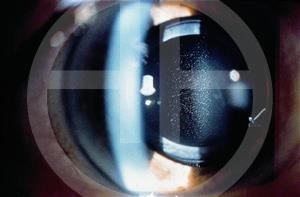

Glistenings

Glistenings are fluid-filled microvacuoles (1- 20 µm) that form within the intraocular lens (IOL) optic when the IOL is in an aqueous environment. It is more commonly seen in hydrophobic IOLs and forms as a result of thermal changes rather than structural changes.[4][15] Glistenings are thought to cause retinal stray light and light scatter and to consequently negatively affect the quality of vision. The only option for a patient with symptomatic glistening is IOL exchange. However, most patients with IOL glistening do not have visual complaints.

Clinical Diagnosis

The key to diagnosis is careful slit lamp examination in high magnification paying special attention to the IOL optic surfaces for signs of granularity or opacification. Slit lamp photography helps to monitor progression. Visual acuity and contrast sensitivity are reduced in IOL opacification cases.